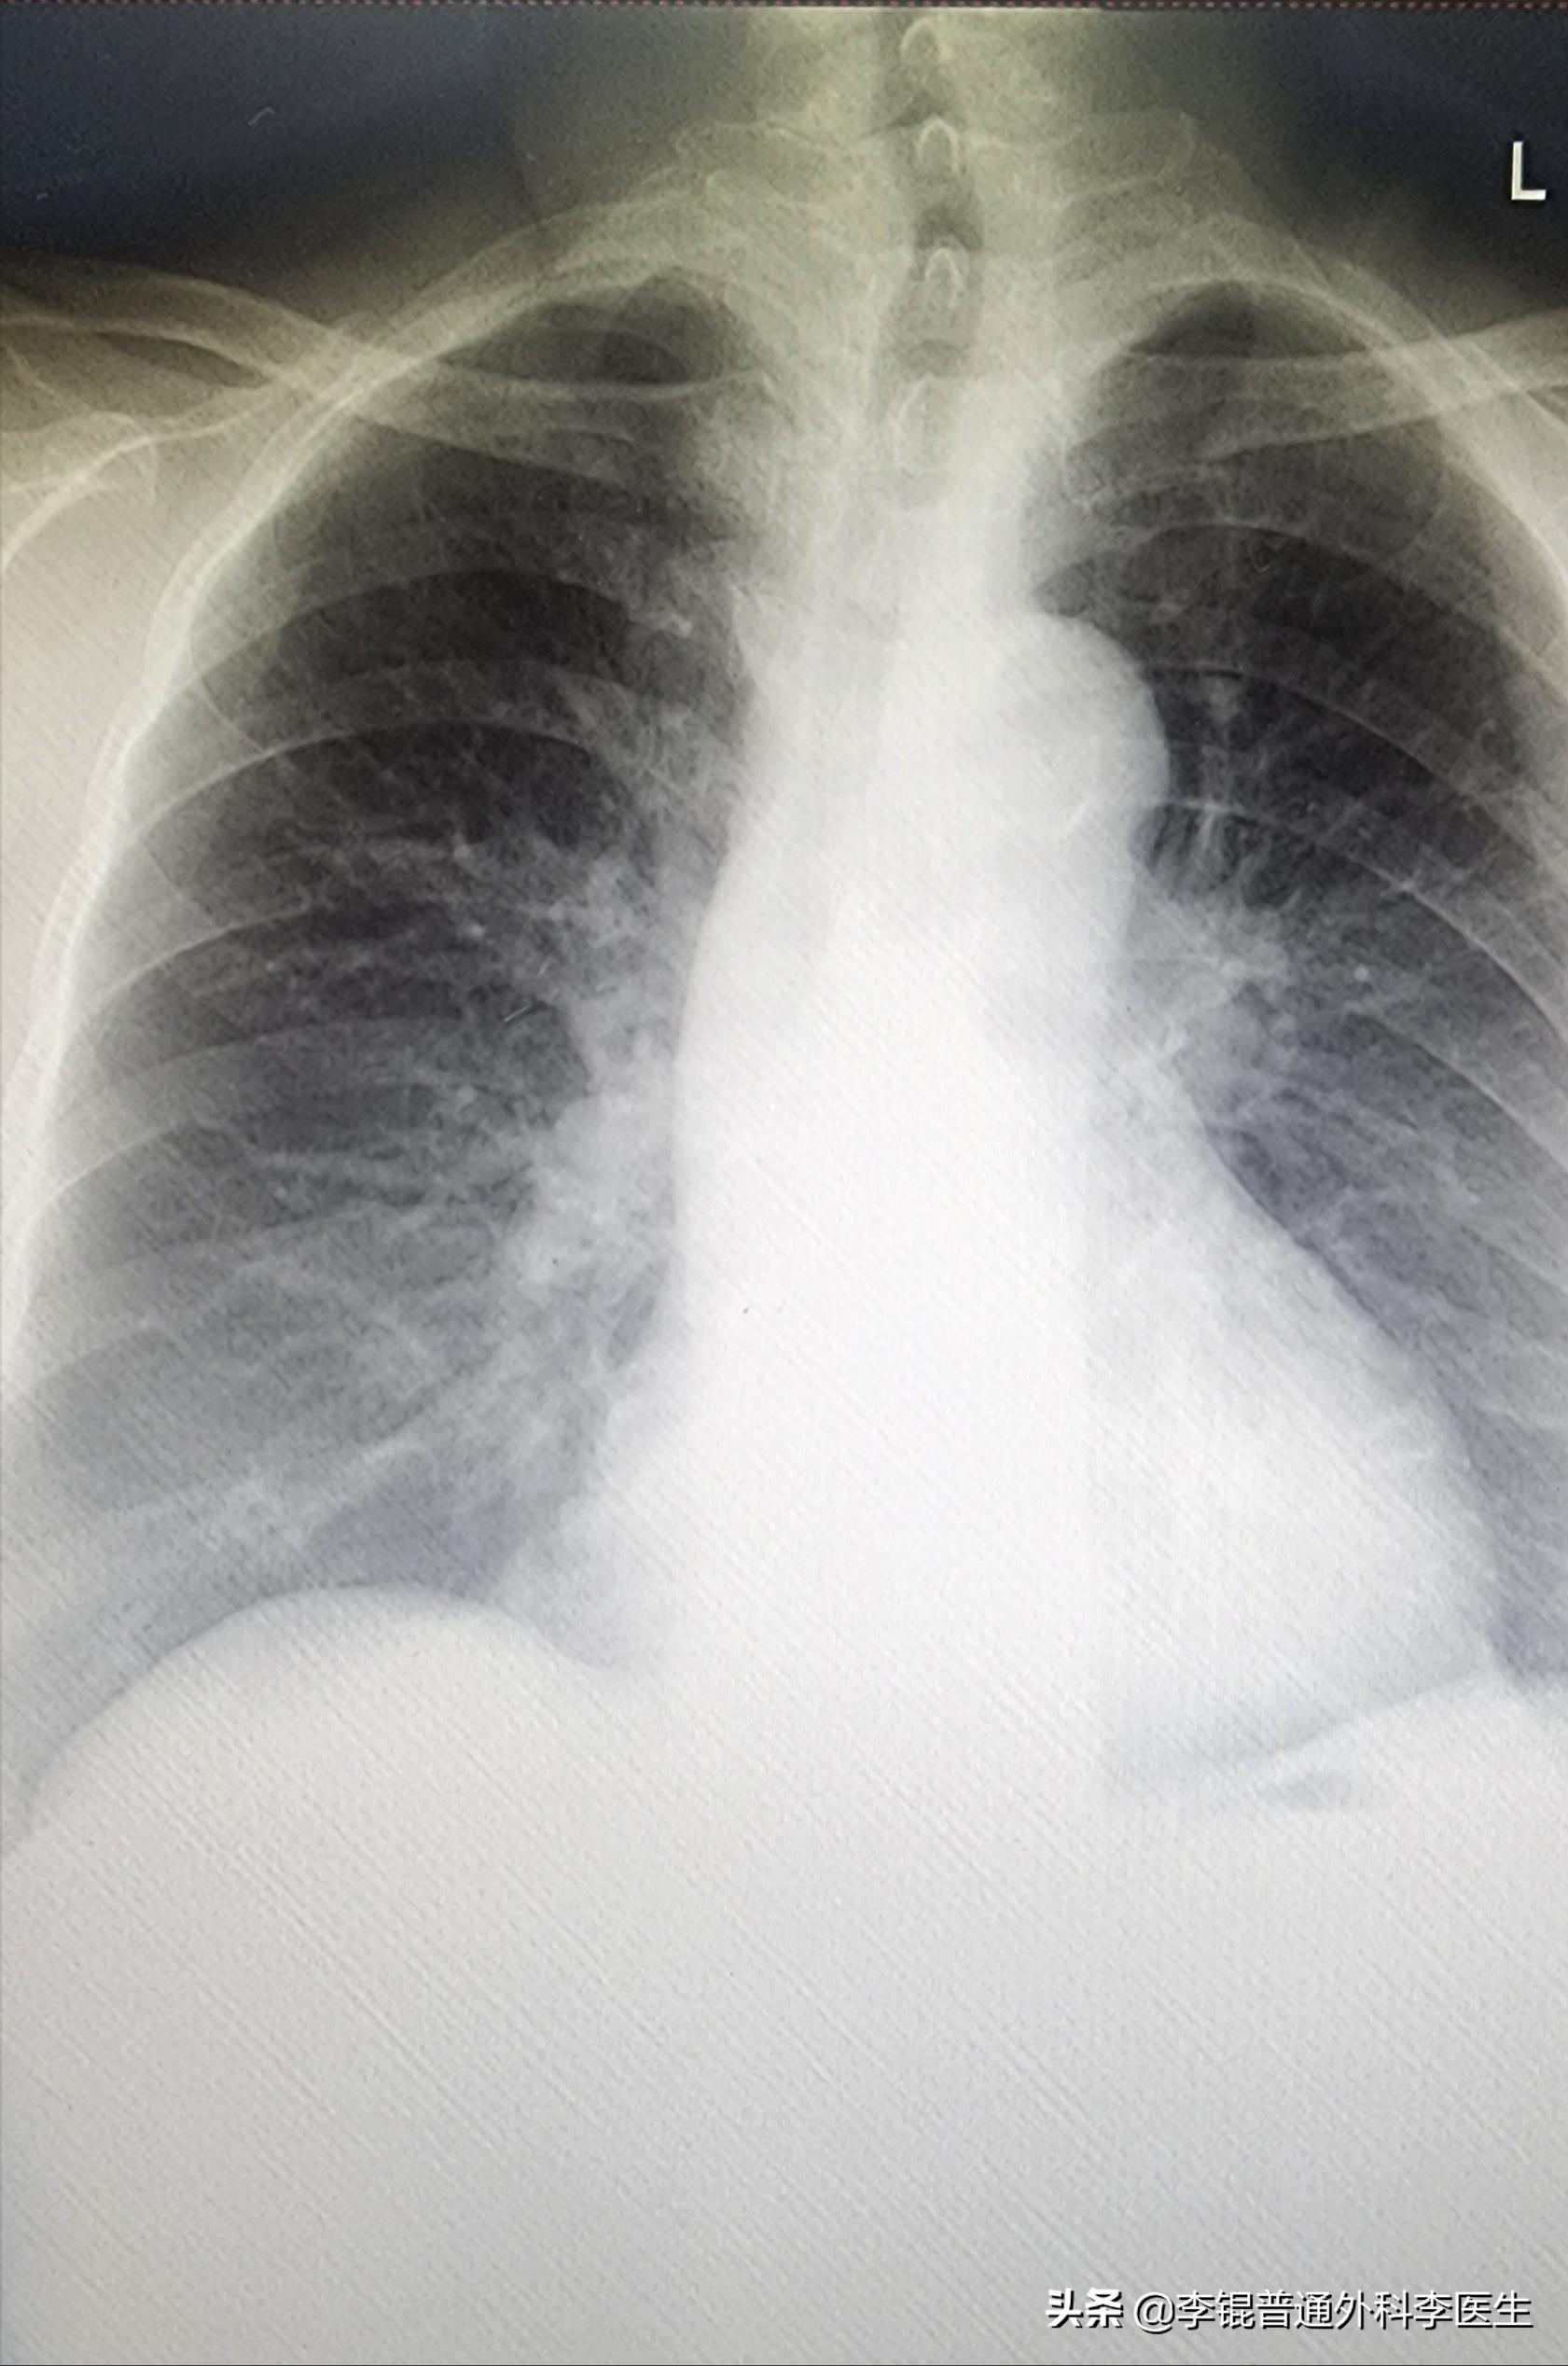

打开了第一张的胸片,一看她的气管形态,我似乎就明白了她为什么会出现这种情况了。

原来在胸片上本来应该差不多是一条直线的大气管在颈部形成了一个明显的S型,并且已经开始变窄了。